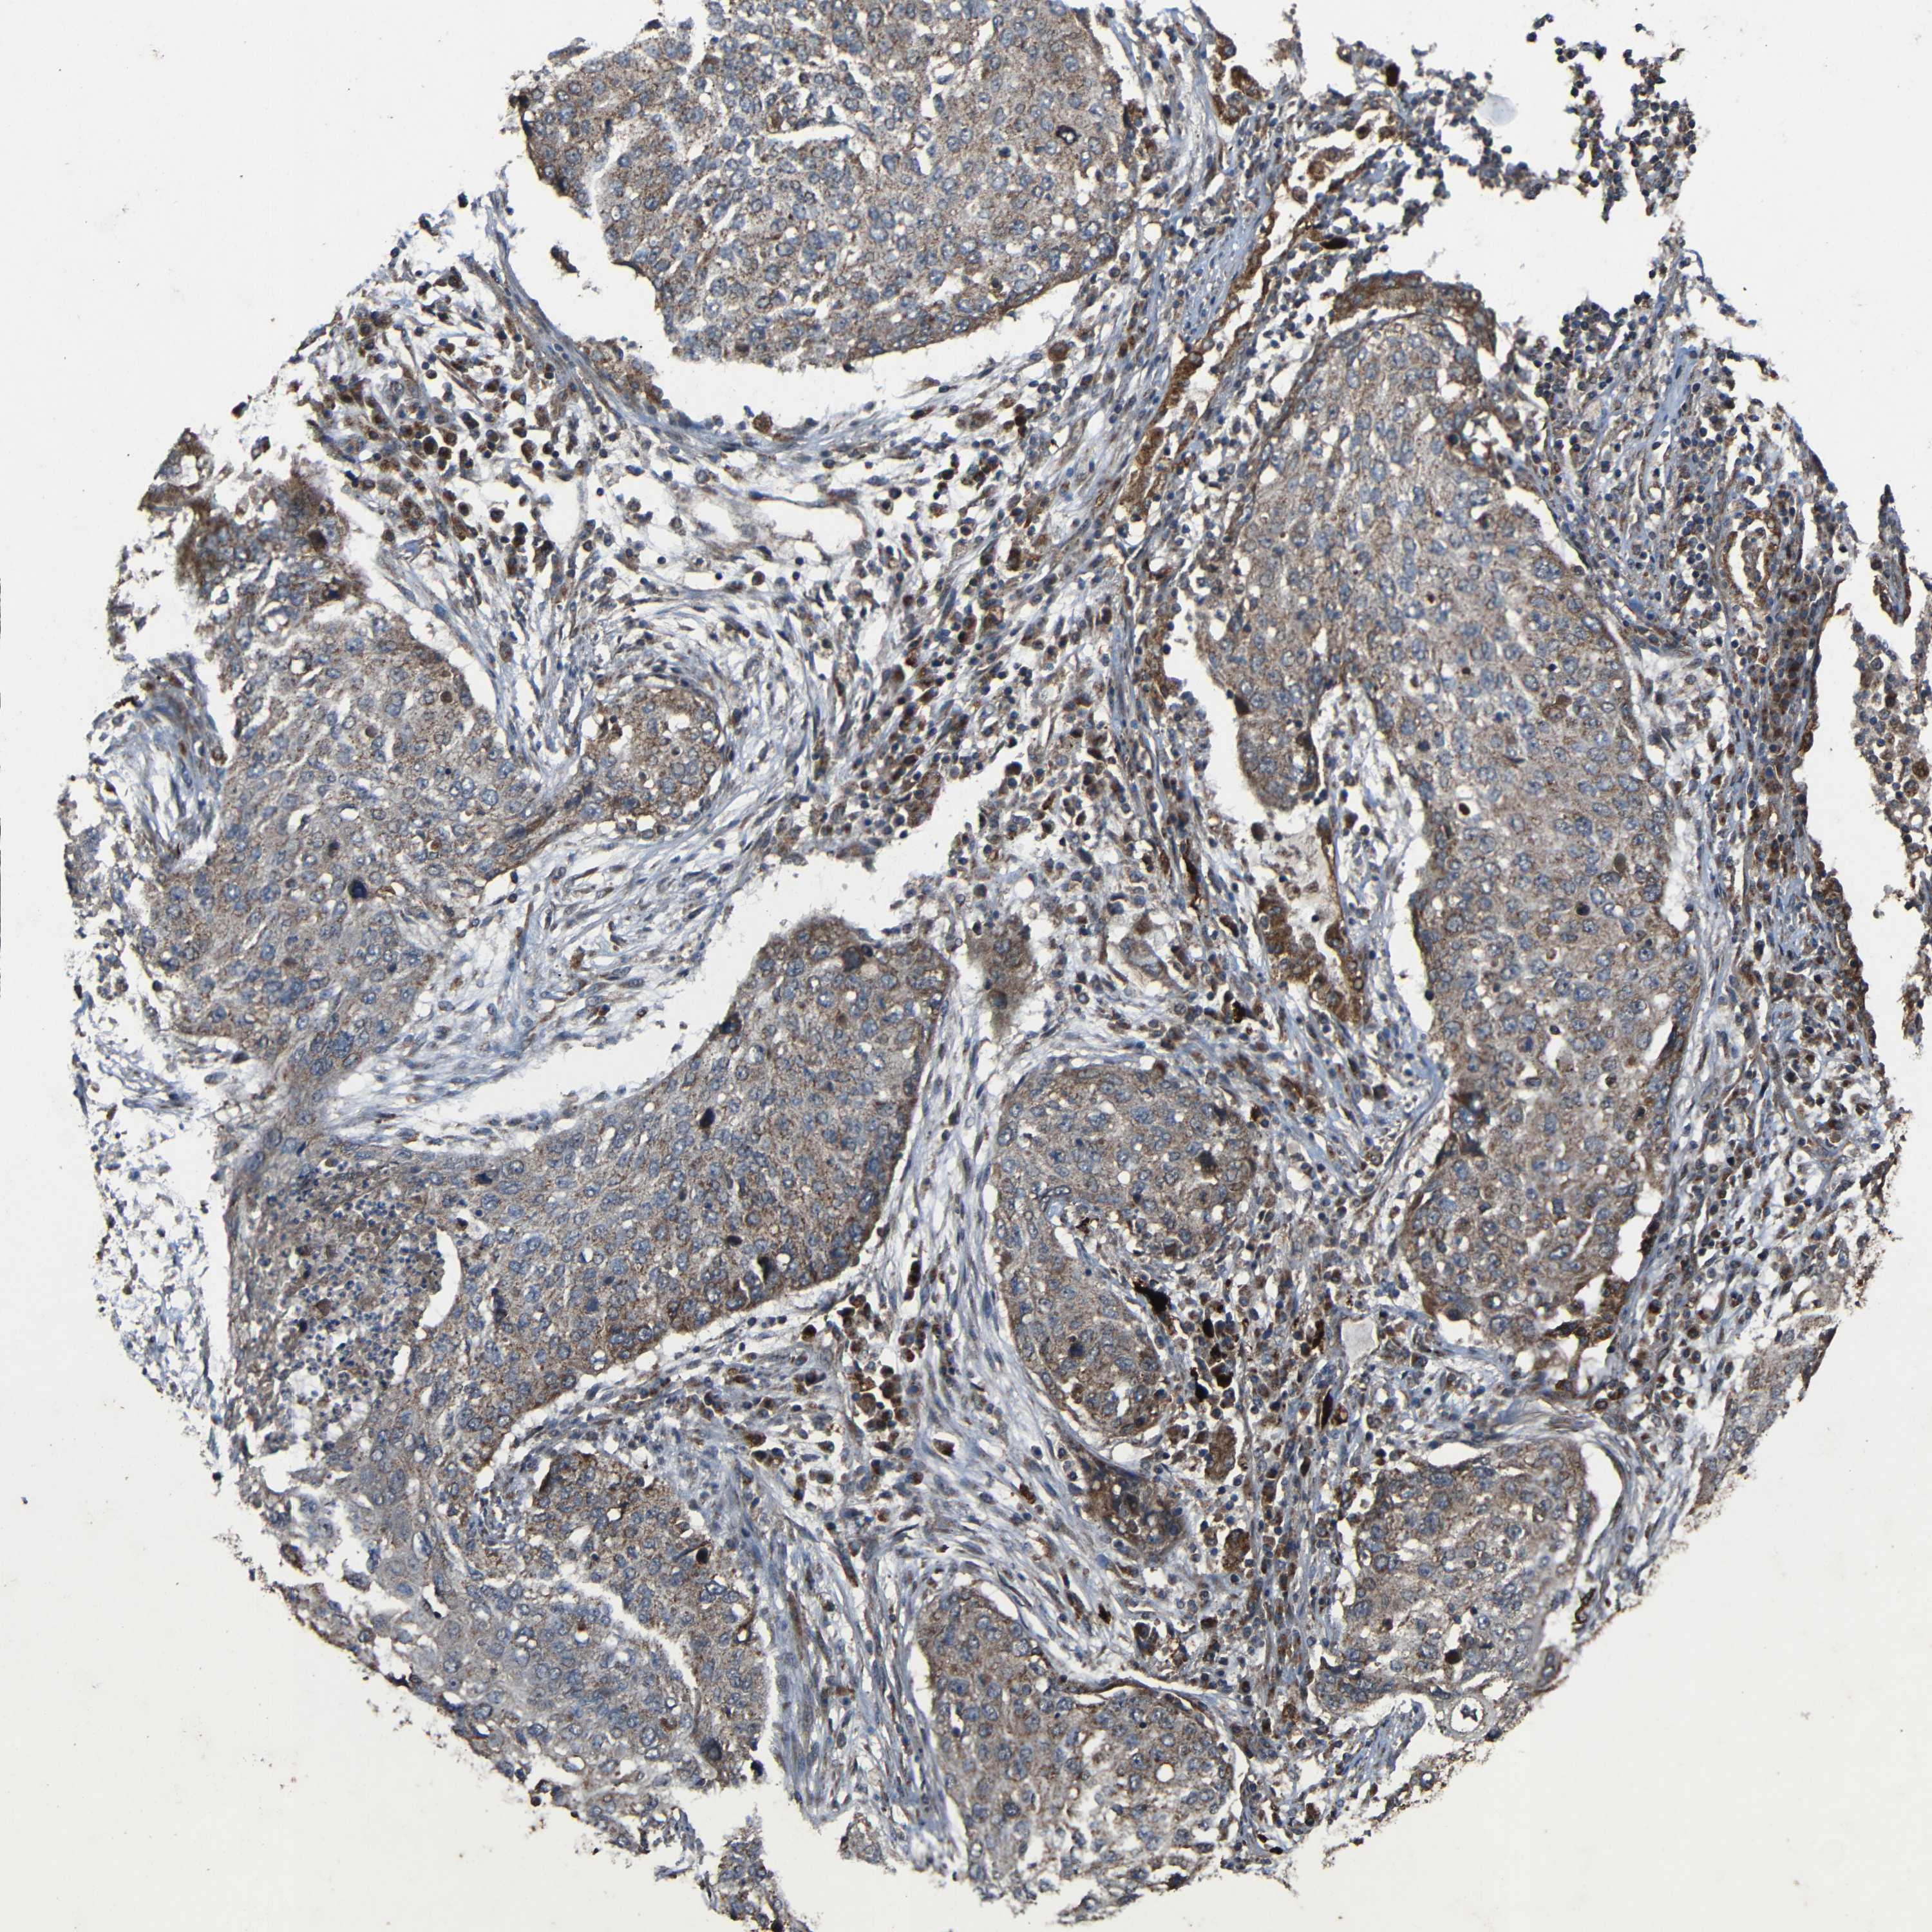

CANCER LUNG CANCER Show tissue menu